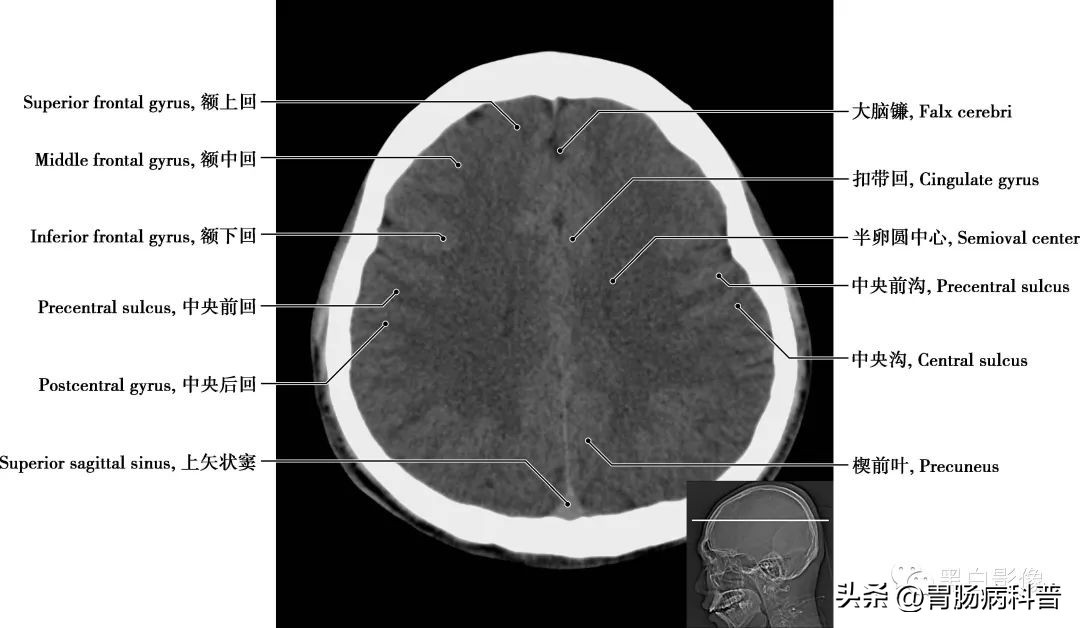

图1-1-6 经扣带回轴位切面

半卵圆中心 为大脑半球中心呈半卵圆形的白质区,主要由胼胝体的辐射纤维以及经内囊的投射纤维等组成。其髓质有三种纤维:①投射纤维,连接大脑皮质和皮质下诸结构,呈扇形放射,称辐射冠;②联络纤维,连接一侧半球内各部皮质区的纤维,人脑联络纤维极为发达,与其他两种纤维相比数量最多;③联合纤维,连接左、右大脑半球相应皮质区